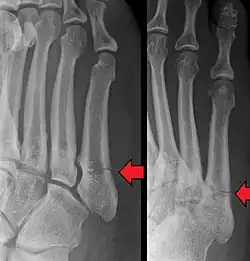

A fratura de Jones é uma fratura óssea entre a base e a parte do meio do quinto metatarso do pé,[1] que resulta em dor, perto da parte do meio de pé do lado de fora.[2] Pode existir também hematomas e dificuldade para andar.[3] O início geralmente é súbito.[4]

O diagnóstico é normalmente baseado na clínica (dor na lateral externa do pé e hematoma após trauma físico) e confirmado com radiografia.[3]